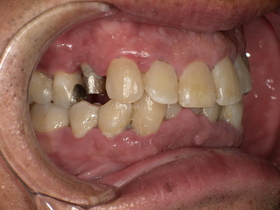

症例結果|Before / After

After

- 自然な白さ

- 違和感ゼロ

- 美しく機能的

👉 見た目も機能も大きく改善